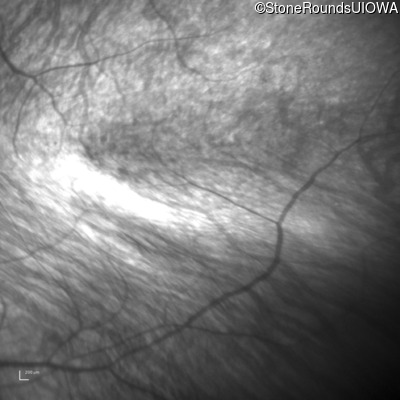

Infrared Fundus Photograph - Right - 10/300 sc

Exemplar